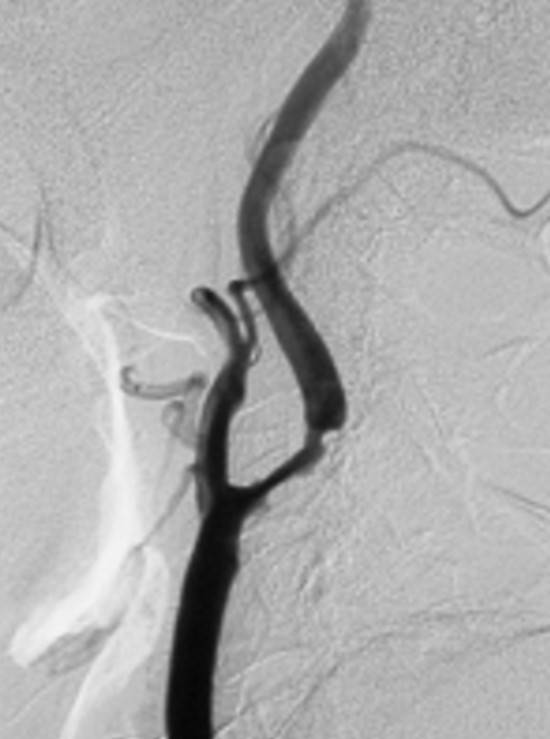

図1:左中等度片麻痺、左同名半盲で発症した脳梗塞症例(74歳男性)の手術前DSA右総頸動脈撮影側面像を提示いたします。右内頸動脈起始部に71%の重度狭窄が見られ、CEAの手術適応があると考えました。(狭窄率の算出法NASCET法= 内頸動脈狭窄部の血管最小径÷狭窄部遠位部の血管径)図2:図1症例の術後DSA右総頸動脈撮影側面像。CEAにより100%以上の血管拡張が得られました。

図1